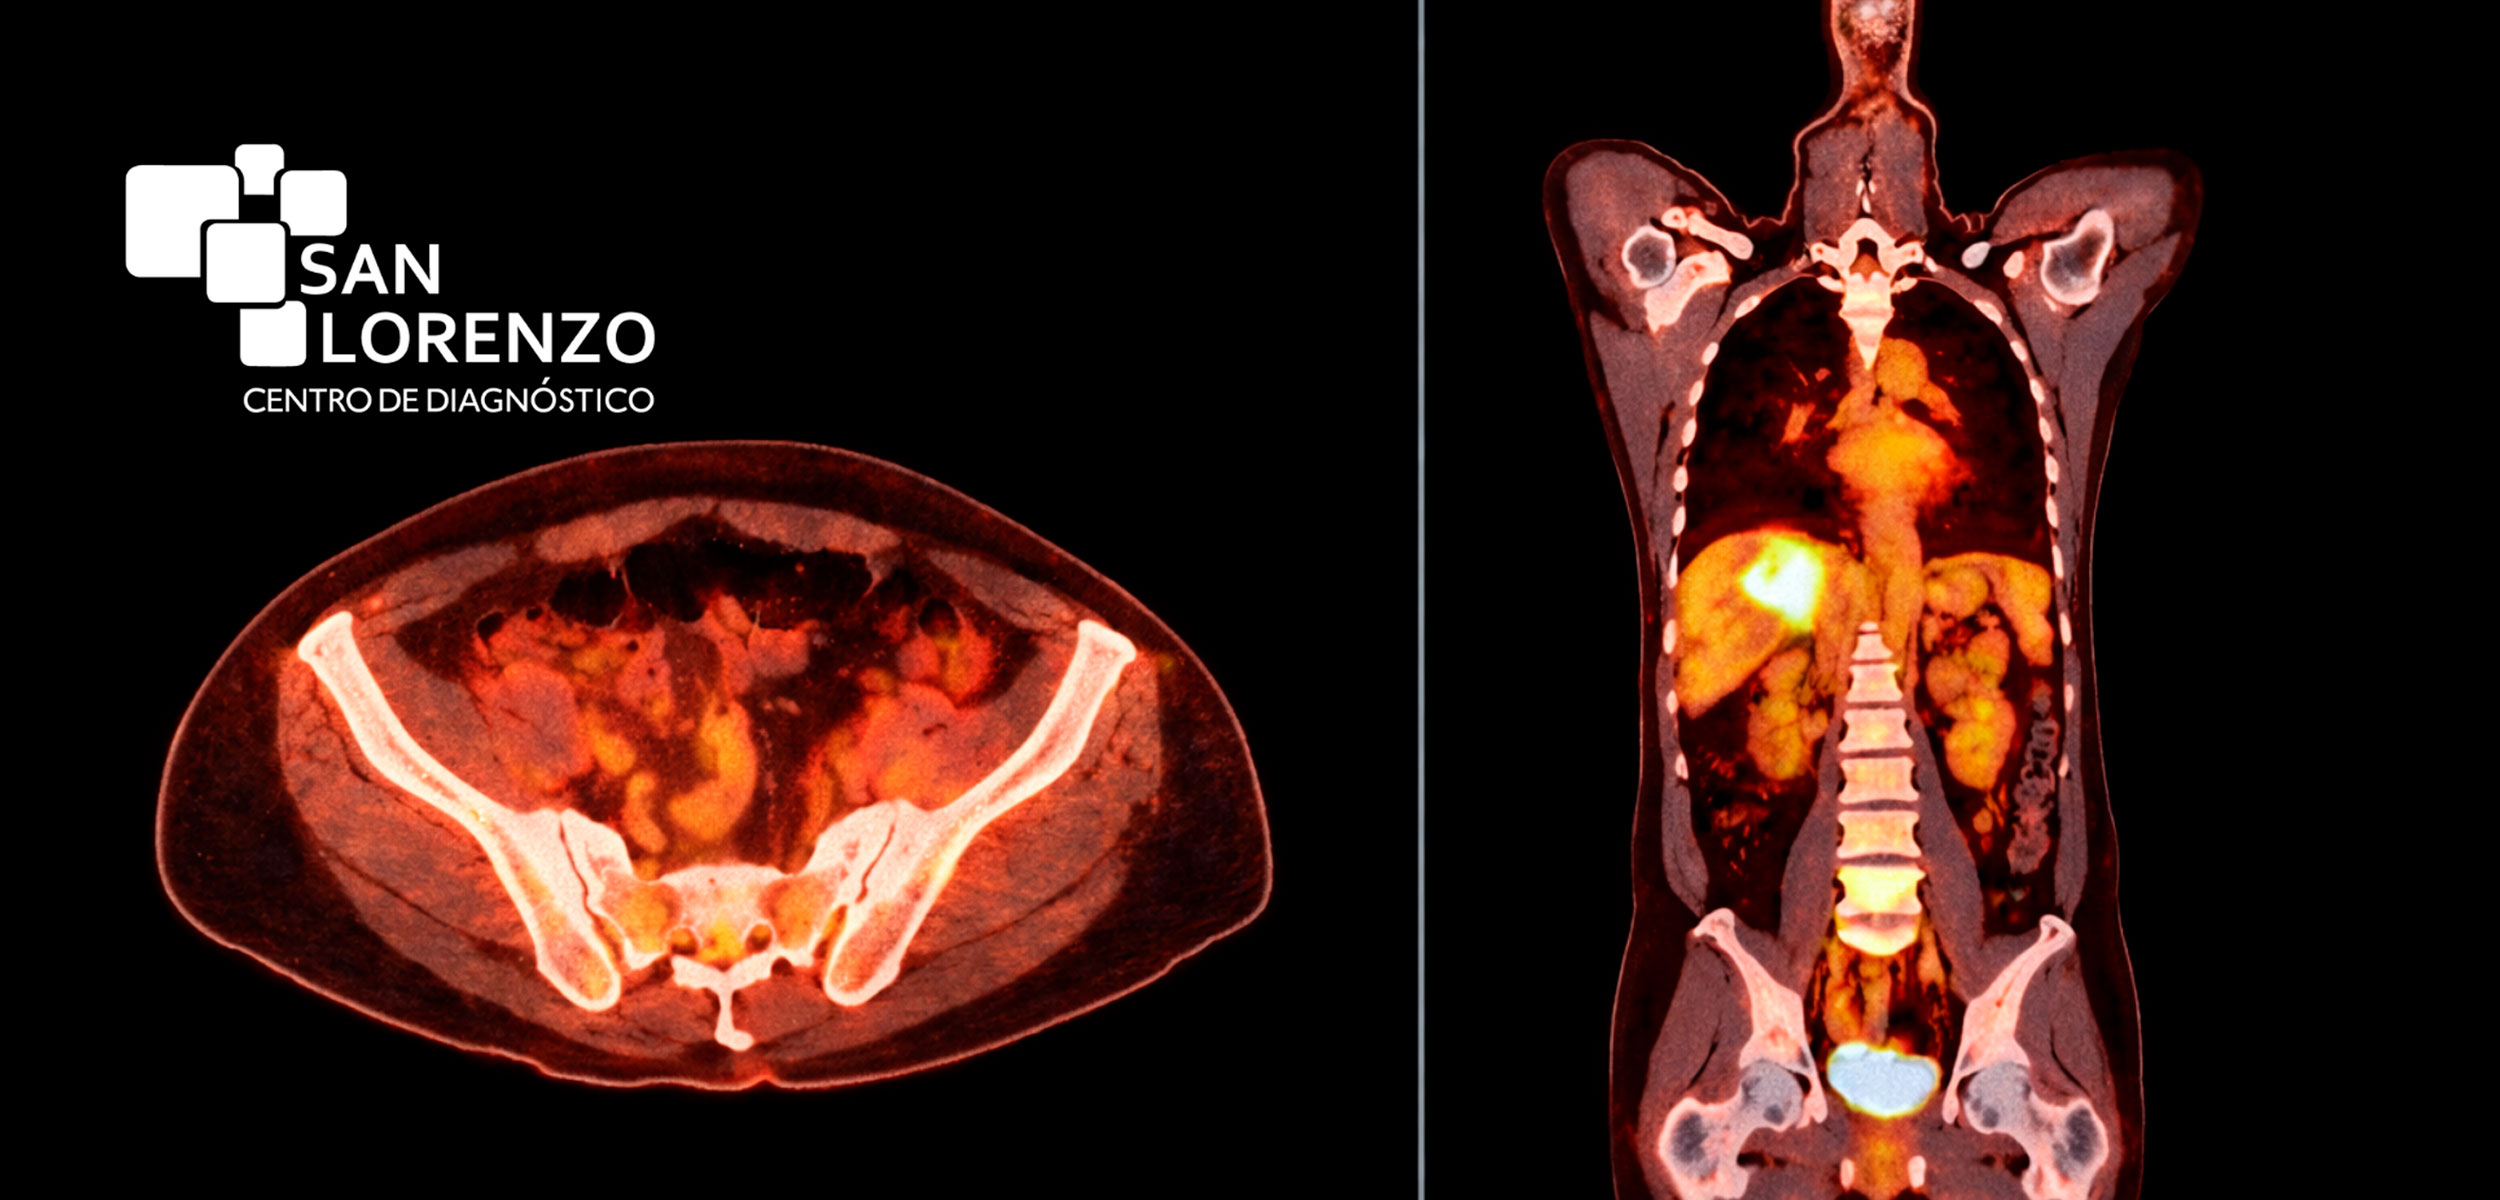

- Scanner (TAC) Multicorte: Fundamental para la detección, etapificación y seguimiento de tumores, con alta velocidad y radiación controlada.